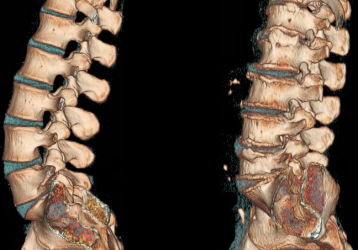

Данное поражение суставов является самым распространенным среди взрослого населения. Оно развивается у любого человека, независимо от возраста (может появляться не только у пожилых людей, но также и у молодежи), пола. Это целый комплекс дистрофических поражений хрящевой ткани. Болезнь имеет характерную особенность — она поражает чаще всего межпозвоночные диски.

Чаще всего это заболевание считается главной причиной появления болевого синдрома в спине. Впервые почувствовать развитие болезни можно уже в 20 лет. Далее, она очень быстро прогрессирует и становится только хуже. Боль является следствием того, что хрящ, который обеспечивает амортизационные свойства позвоночника, истончается. Диски сильно прижимаются друг к другу и поддаются трению, доставляя человеку дискомфорт.

1. Остеохондроз поясничного отдела (встречается очень часто).